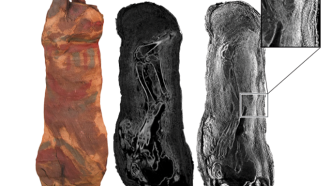

Images made with these particles have revealed details of dinosaur bones, mummies and more.